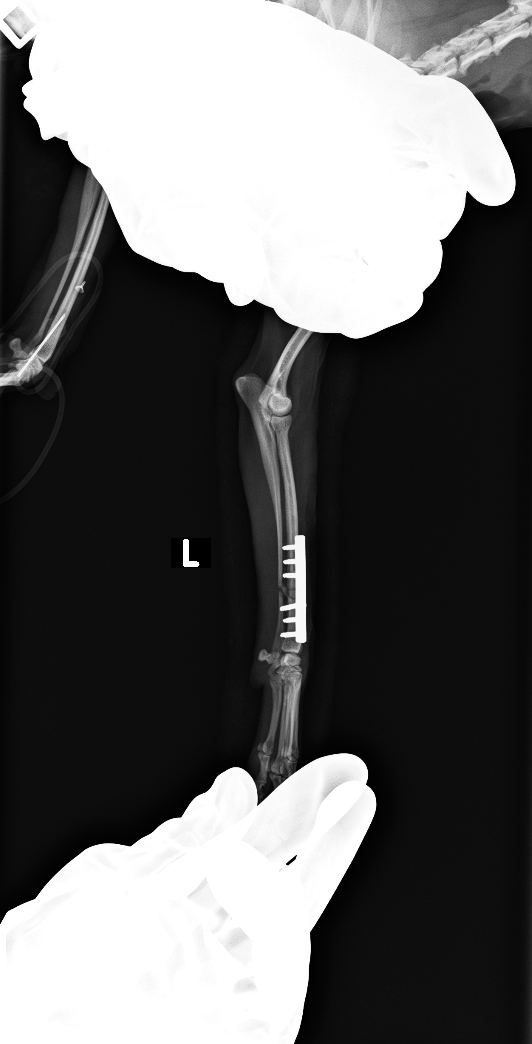

右上腕骨頭において、2.0のドリルビットを用いて皮質骨を貫通し、キュレットで海面骨を採取した

2.0のカッタブルプレートを使用し、コンベンショナルスクリューを用いた

after